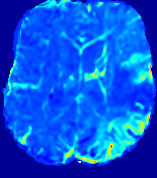

LesionRefer to captionRefer to captionRefer to captionRefer to captionRefer to captionRefer to caption𝐕rgbsubscript𝐕𝑟𝑔𝑏{\bf{V}}_{rgb}Refer to captionRefer to captionRefer to captionRefer to captionRefer to captionRefer to caption𝐕2subscriptnorm𝐕2{\|\bf{V}}\|_{2}Refer to captionRefer to captionRefer to captionRefer to captionRefer to captionRefer to captionRefer to caption3.53.53.52.82.82.82.12.12.11.41.41.40.70.70.70.00.00.0(mm/s)𝑚𝑚𝑠(mm/s)D𝐷DRefer to captionRefer to captionRefer to captionRefer to captionRefer to captionRefer to captionRefer to caption0.0200.0200.0200.0160.0160.0160.0120.0120.0120.0080.0080.0080.0040.0040.0040.0000.0000.000(mm2/s)𝑚superscript𝑚2𝑠(mm^{2}/s)Slice #1Slice #2Slice #3Slice #4Slice #5Slice #6

Figure 3: PIANO feature maps for one stroke patient, where the lesion is located in the left hemisphere. Top row: segmented stroke lesion region (white) on different slices, obtained from ISLES 2017. The corresponding slices for the PIANO feature maps are shown in the following rows.

For a better insight into an estimated velocity field 𝐕𝐕{\bf{V}} and diffusion field 𝐃𝐃{\bf{D}}, we compute the following maps: (1) 𝐕rgbsubscript𝐕𝑟𝑔𝑏{\bf{V}}_{rgb}: Color-coded orientation map of 𝐕=(Vx,Vy,Vz)T𝐕superscriptsuperscript𝑉𝑥superscript𝑉𝑦superscript𝑉𝑧𝑇{\bf{V}}=(V^{x},V^{y},V^{z})^{T}, obtained by normalizing 𝐕𝐕{\bf{V}} to unit length and mapping its 3 components to red, green, blue respectively; (2) 𝐕2subscriptnorm𝐕2\|{\bf{V}}\|_{2}: 222 norm of 𝐕𝐕{\bf{V}}; (3) D𝐷D: scalar field in Eq. 5.

Fig. 3 and Fig. 4 show the PIANO feature maps estimated from two ISLES 2017 patients: all are highly consistent with the lesion in both cases. Details of the blood flow trajectories are revealed in 𝐕rgbsubscript𝐕𝑟𝑔𝑏{\bf{V}}_{rgb} by the ridged patterns and the sharp changes of colors in the unaffected (right) hemisphere, while the flat patterns appearing within the lesion provide little directional information about the velocity and indicate low velocity magnitudes. Velocity magnitudes are more directly visualized via 𝐕2subscriptnorm𝐕2\|{\bf{V}}\|_{2}, from which one can easily locate the lesion where 𝐕2subscriptnorm𝐕2\|{\bf{V}}\|_{2} is low. D𝐷D also indicates lower diffusion values in the lesion, though with less contrast potentially due to the fact that it captures the accumulated effect of CA diffusion at the voxel-level.